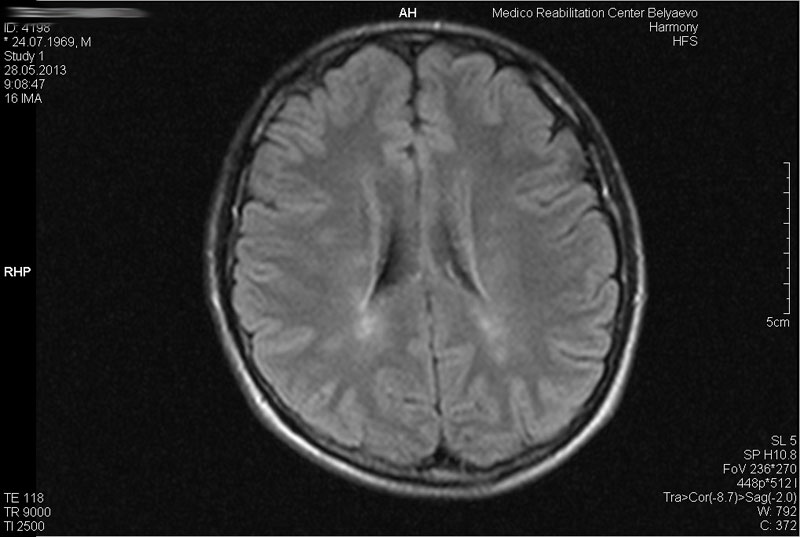

Примеры МРТ-исследования

МРТ головы – это метод медицинской визуализации головного мозга и окружающих тканей с использованием магнитного поля, без ионизирующего излучения.

МРТ головы позволяет получить качественные изображения мозга и окружающих тканей. МРТ головы можно использовать для диагностики и мониторинга многих заболеваний и состояний , в том числе: